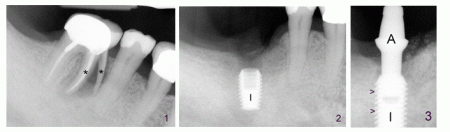

陳先生一顆下磨牙出現疼痛,因為其中一個牙根裂開(圖一:*),不得不拔除,植牙(圖二:I)。當植牙癒合後(骨頭長入植牙螺紋(圖三:箭頭)),基牙(A)一頭插入植牙中,另外一頭穿過牙齦(圖四: T/L),暴露於口腔之中,然後戴上牙冠(圖五:C)。

植牙和牙齒鄰近牙齦特別厚(圖四,圖五:T),不容易移動,像手掌的厚皮膚,能承受牙冠/牙齒咬合面咀嚼後食物直接衝擊,而遠離植牙牙齒的牙齦(L)就比 較薄、鬆動,就象林黛玉的手背的皮膚。但是細皮嫩肉的牙齦也有它功能,因為它鬆軟,在肌肉幫助下,把丟在那裡的食物推回到咬合面,再次咀嚼,最後把食物碾 碎。

缺牙若干時間後,厚的牙齦因為失去咀嚼刺激而萎縮,變成薄的牙齦,植牙周圍厚牙齦就比牙齒周圍厚牙齦窄(圖四圖五)。如果植牙前厚牙齦太少,牙醫可能會建議先植皮。植皮也可以治療牙齦萎縮。總之,拔牙後,骨頭和牙齦一起會萎縮,我們應該及早植牙。